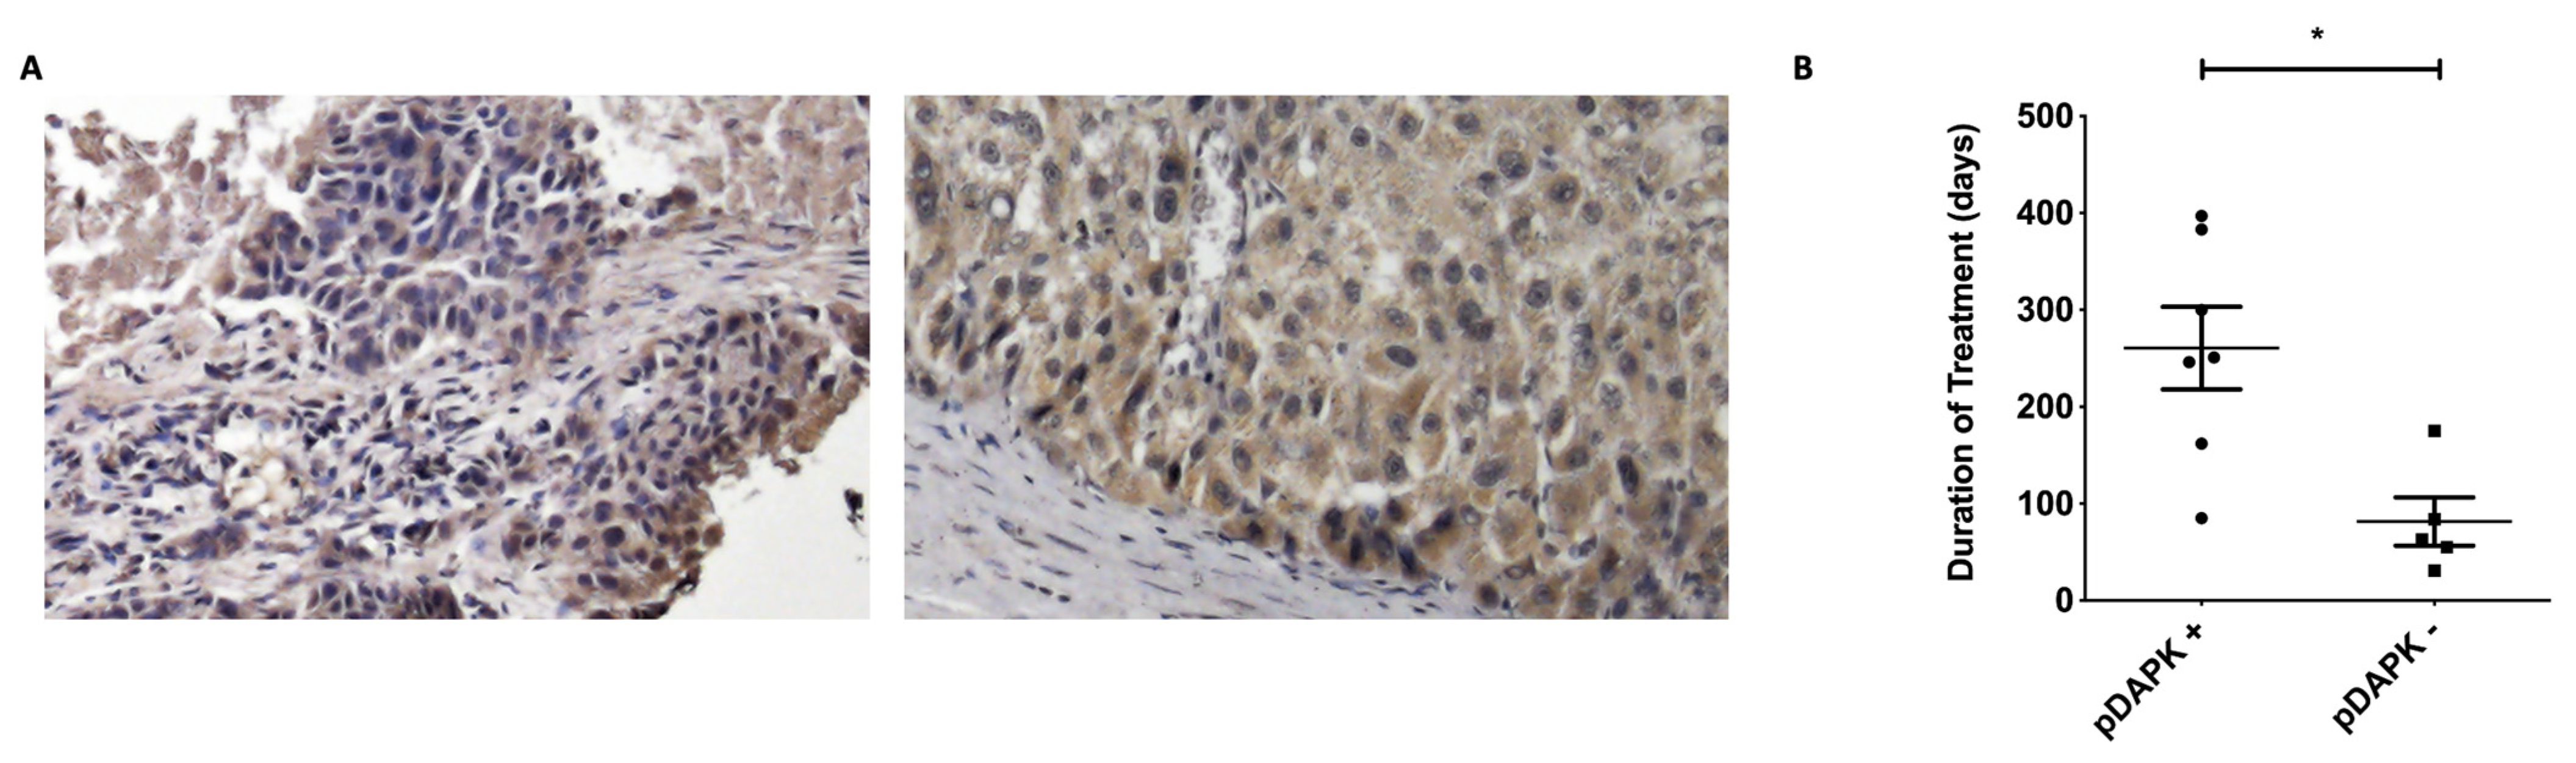

3.5. DAPK Expression in Primary vs. Metastatic Tumor